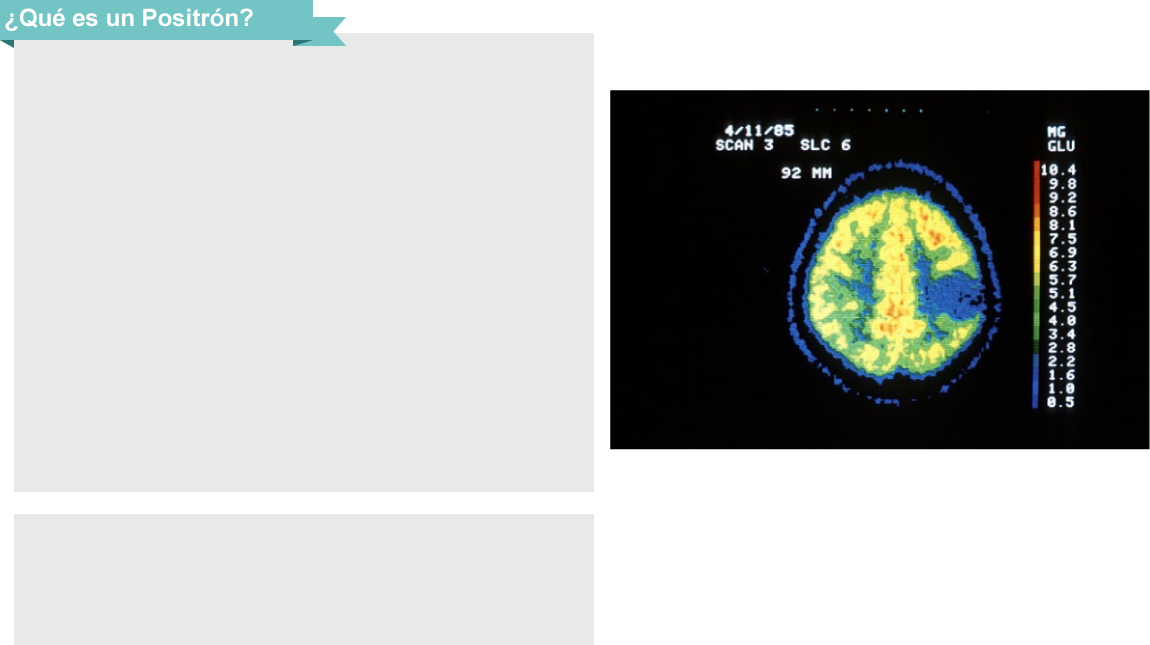

Al unirse un positrón con un electrón se libera

energía en forma de rayos gamma que es captada

por sensores de rayos gamma cuando el detector

recibe la señal , manda información a un computador

que procesa los datos para crear una imagen

bidimensional que se observa en el computador